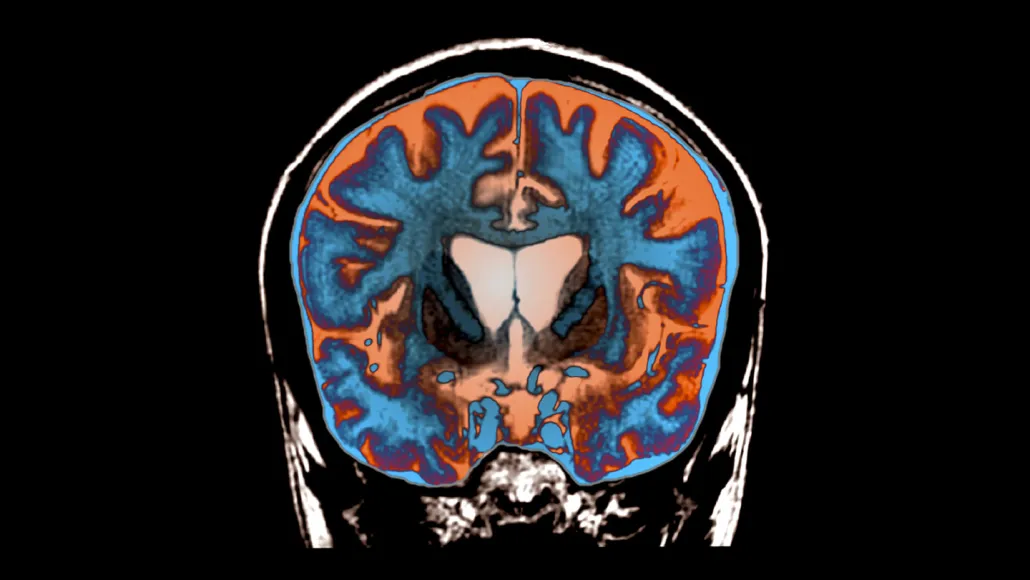

Huntington's is caused by a single genetic mutation: an expanded CAG repeat in the HTT gene that produces a toxic form of the huntingtin protein. This misfolded protein gradually destroys neurons in the striatum, the brain region responsible for movement control, leading to the involuntary movements, cognitive decline, and psychiatric symptoms that define the disease. Most people with Huntington's begin showing symptoms in their 30s or 40s and die within 10 to 20 years of onset.

AMT-130 works by silencing the mutant HTT gene at the source. The therapy uses an adeno-associated virus (AAV) vector — a modified, harmless virus — to deliver a microRNA that specifically targets and degrades the messenger RNA produced by the faulty gene. Without that mRNA, cells can't make the toxic protein in the first place. The treatment is delivered directly into the striatum via a neurosurgical procedure lasting eight to ten hours.